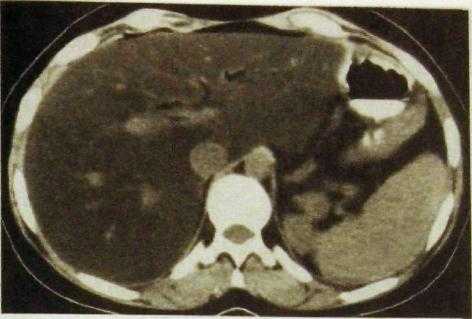

Диффузные поражения печени. Точная диагностика диффузных поражений основывается на анамнестических и клинических данных, результатах биохимических исследований и в ряде случаев пункционной биопсии печени. Лучевые методы обычно играют лишь вспомогательную роль. Исключением является жировой гепатоз. Жир поглощает рентгеновское излучение хуже, чем остальные мягкие ткани, поэтому тень печени при жировом гепатозе на компьютерных томограммах характеризуется низкой плотностью (рис. Ш.136).

Рве. III. 136. Компьютерная томограмма печени. Жировой гепатоз: низкая плотность печеночной ткани.